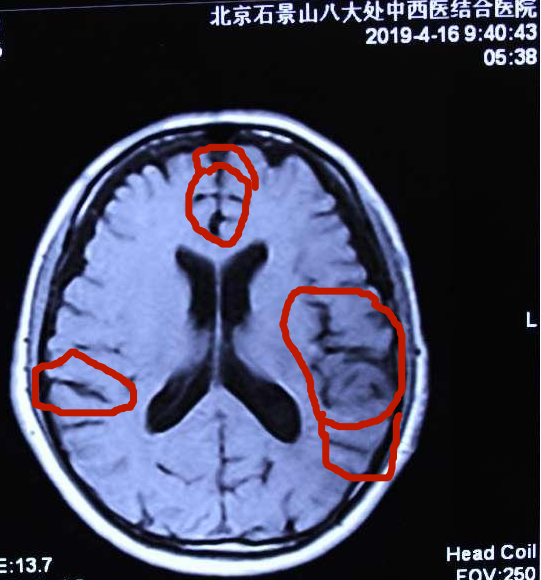

张先生阿尔茨海默症典型病例治愈简介: 2019年4月16日接诊。接诊地点:北京石景山八大处中西医结合医院贾学铭教授诊室。 患者:张先生男71岁 头晕多年,近3年经常头晕头痛,近一年病情渐渐加重,记忆障碍严重减退,对事情过后即忘,当天上午吃的的早餐不记得,过后又要吃早餐等,对刚刚放下的物品回头即忘,经北京多家大医院诊断为:阿尔茨海默症,经过多种方法治疗无效,而来要求治疗。2019年4月16日北京八大处中西医结合医院核作磁共振显示:多发性脑梗塞,脑萎缩,给以纯中药治疗经过57天,头晕头痛消失,记忆恢复正常,对近3天的早餐记得非常清楚,以前忘记的事情也想得清楚,肢体麻木消失,行走活动正常,面部的老年斑也渐渐消退,精神非常好。2019年7月9日北京八大处中西医结合医院做核磁共振与治疗前2016年4月16日的影像比较,显示:多发性脑梗塞明显消失,脑萎缩明显恢复。治疗结果:阿尔茨海默症病情治愈。以下是核磁共振片治疗前后的对比: 张先生阿尔茨海默症治愈前后拍核磁共振片比较,要观察细节:

治疗前脑萎缩严重明显(原始整张片)。 治疗后脑萎缩明显恢复(原始整张片)。

张先生核磁共振片其中单图的治疗前后比较:

2019年4月16日前见片治疗脑萎缩严重。病情严重。 2019年7月9日治疗后见片脑萎缩减轻。病情治愈。

脑组织逆生长的情况见左右两个图内红圈相对等部位的比较,圈内白色的部分是脑组织,圈内黑色的部分是没有脑组织了是萎缩后空缺的现象,黑色越多脑萎缩越严重,白色越多脑组织越多,脑组织多了,就是改变了脑萎缩,就是脑组织逆生长,因此,通过中药使脑组织逆生长就消除了和治愈了脑部的疑难病。该患者的阿尔茨海默症通过纯中药达到了脑组织逆生长,患者的记忆障碍就正常了,病情就治愈了。 实践证明阿尔阿尔茨海默症的发病,不仅是现代医学认为的海马体萎缩的问题,是脑部整体出现了问题,也不是不可治愈的疾病,是能够治愈的。我们经过几十年的研究探讨创新,用纯中药治愈阿尔茨海默症是科学的真实有效的!只要是脑组织逆生长,阿尔茨海默症就必然能够治愈。 |